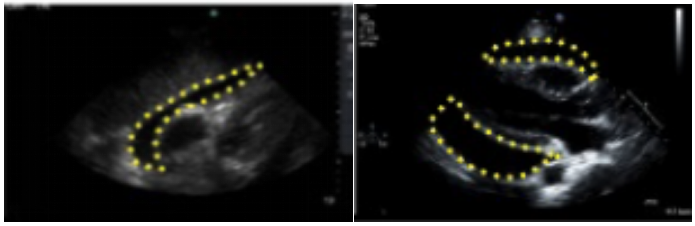

(1)左心射血分数(LVEF):最常用的一个值,通常采用心尖双平面改良Simpson法图21或者Teichholtz法(图22)测量。若有心肌节段运动异常,推荐Simpson法,在心尖四腔心切面或心尖两腔心平面,利用超声系统自带的软件,描记左心室在收缩末期和舒张末期的边界,设备自动算出LVEF值。若无心肌节段运动异常,可采用M超胸骨旁长轴切面Teichholtz法来测量,取样线垂直于室间隔和左室后壁。Teichholtz法的LVEF计算公式为:

图片

图21. Simpson法在A4C切面或A2C切面测量LVEF

(4)左室短轴切面面积变化分数(LV-FAC%):在胸骨旁短轴(PSAX)乳头肌切面(图24),清晰显示心内膜以后,分别勾勒左室舒张末面积(LVEDA)和左室收缩末面积(LVESA),通过下面公式进行计算:

LV-FAC%=(LVEDA-LVESA)/LVEDA×100%

LVFAC%的参考值为50%~75%。

图24. PSAX乳头肌切面测量LVEA